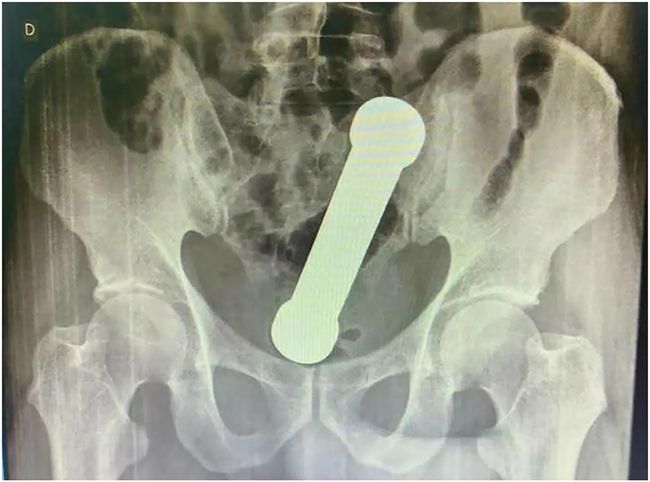

Viral hasil X-ray barbel nyangkut dalam anus. (Foto: International Journal of Surgery Case Reports)

Dokter awalnya melakukan pemeriksaan awal atas keluhan sang pasien, namun tak menghasilkan apa-apa. Dokter kemudian memutuskan untuk memeriksa pasien itu dengan x-ray atau sinarx.

Mereka menemukan barbel sepanjang 20 cm bersarang di persimpangan usus besar dan dubur seperti mainan seks yang rumit.